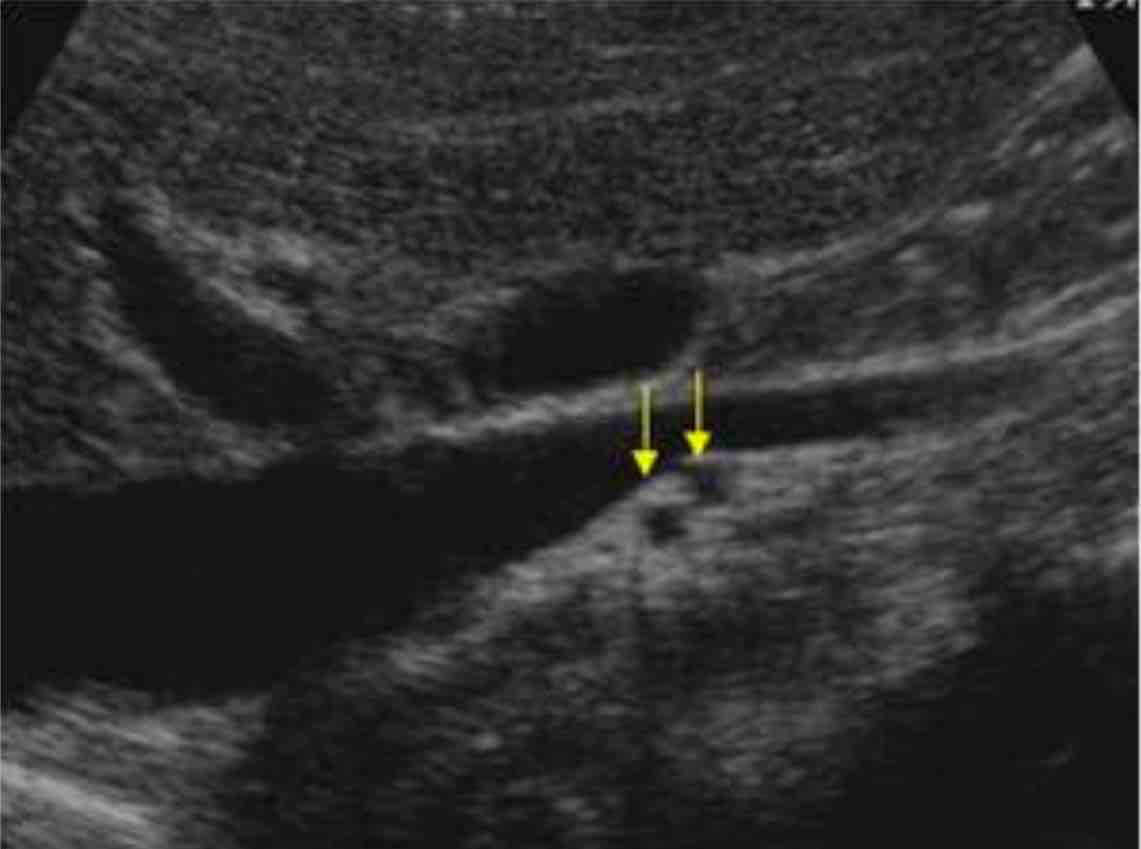

what plane is this image taken in? arrows are pointing to what vessels?

2 right renal arteries